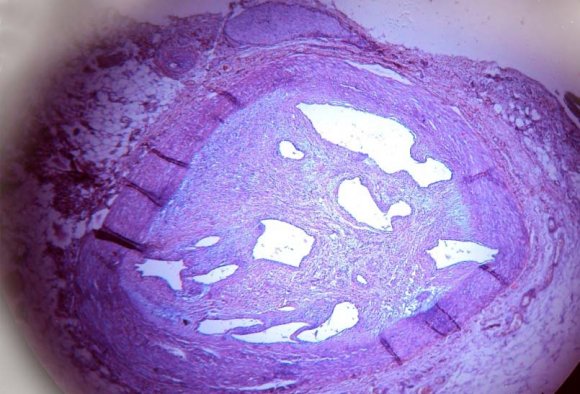

The methods used for the analysis of the material was as per the procedure recommended by 1. White, Edward and Dry (1950). 2. Gore and Tejada (1957). All autopsies were carried out within four to twenty four hours after death. 10,11,12 All the specimens of right and left coronary arteries blocks were taken at a particular fixed distance at from 1.5 cm and 3 cm from the Ostia, also From the circumflex branch of the left coronary artery, bits were taken at the same distance form the point of branching of the left coronary artery into anterior descending and circumflex branches. Additional bits of tissue were taken from other regions of the vessels which showed stenosis. This stenosis is graded based on the luminal narrowing of the coronaries when examined by hand lens and is graded from grade 0 (no narrowing / normal) to grade IV (complete obliteration). Grade -0 : Normal Grade -I : 1-25% stenosis Grade -II : 26-50% stenosis Grade -II : 51-75% stenosis Grade -IV : 76-100% stenosis The bits of the tissue were fixed in 10% formalin and embedded in paraffin. Sections for histological study were taken from the paraffin blocks and stained with haematoxylin and eosin. Special stains were also done whenever indicated, namely Verhoeff and Van-Gieson's for demonstration of elastic tissues, smooth muscle and collagen, and Alcain blue for the demonstration of mucopolysaccharide ground substance. All histological sections were studied for microscopic evidence of atherosclerotic lesions.

Of the 50 heart specimens studied 33 showed coronary atherosclerosis with various histological changes such as fibroblastic activity, mucopolysaccharide deposition, degeneration of internal elastic lamina, accumulation of lipid cholesterol crystals, hyalinization, calcification and hemorrhage. Salient features of atherosclerotic lesions i.

Fatty streaks. ii.

Fibrous plaques. iii.

Atheroma. Histological, examination of representative plaques in the second and third decades showed the presence of fat with little or no cellular reaction. In the 4 th and 5 th decades, there was generally a fibrous tissue reaction to the presence of fat. By the 5 th decade, the fibrous reaction had become more pronounced and was associated with degenerative changes.